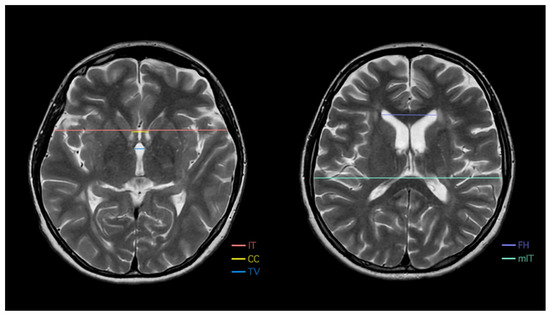

| FH | Frontal horn distance |

| CC | Intercaudate distance |

| TV | Third ventricle width |

| IT | Inner table of the skull |

| mIT | Maximum inner table of the skull |

| BCR | Bicaudate ratio |

| Frontal horn width (FH) [mm] | |||||||

| Intercaudate distance (CC) [mm] | |||||||

| Inner table of the skull measured along the CC line (IT) [mm] | |||||||

| Inner table of the skull measured at its maximum width (mIT) [mm] | |||||||

| Third ventricle (TV) [mm] | |||||||

| Bicaudate ratio (BCR) | |||||||